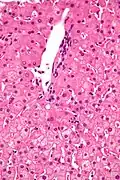

In liver pathology, a ground glass hepatocyte, abbreviated GGH, is a liver parenchymal cell with a flat hazy and uniformly dull appearing cytoplasm on light microscopy. The cytoplasm's granular homogeneous eosinophilic staining is caused by the presence of HBsAg.

The appearance is classically associated with abundant hepatitis B antigen in the endoplasmic reticulum, but may also be drug-induced.[1][2] In the context of hepatitis B, GGHs are only seen in chronic infections, i.e. they are not seen in acute hepatitis B.

Micrograph showing ground glass hepatocytes. H&E stain. -